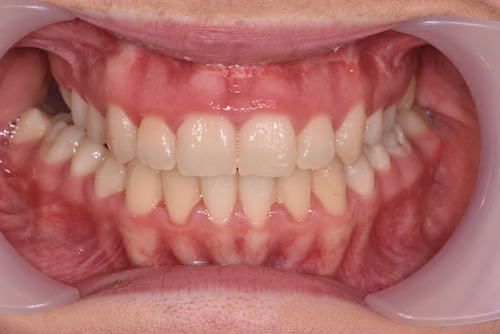

When the bones of the face and jaws are out of balance with each other, orthodontics alone will often not be able to position the teeth in order to create a functional bite. This imbalance between the jaws can result in a combination of problems. These may include:

Surgery may involve either the upper jaw, lower jaw or both depending on the skeletal discrepancy of your particular case. This will allow the teeth to meet correctly and provide you with an improved bite, and often there is an accompanying improvement in your facial appearance and profile.

Your teeth need to be aligned, levelled and moved into the correct position ready for your jaw surgery to take place and remain stable after the surgery. This can often result in your bite becoming worse over the period of orthodontic treatment, but you have to remember that your teeth will be in a better, more stable position after the jaws have been moved into their correct planned position.

- Improved facial appearance

- Improved function – better bite, no pain / trauma on biting

- Straight teeth